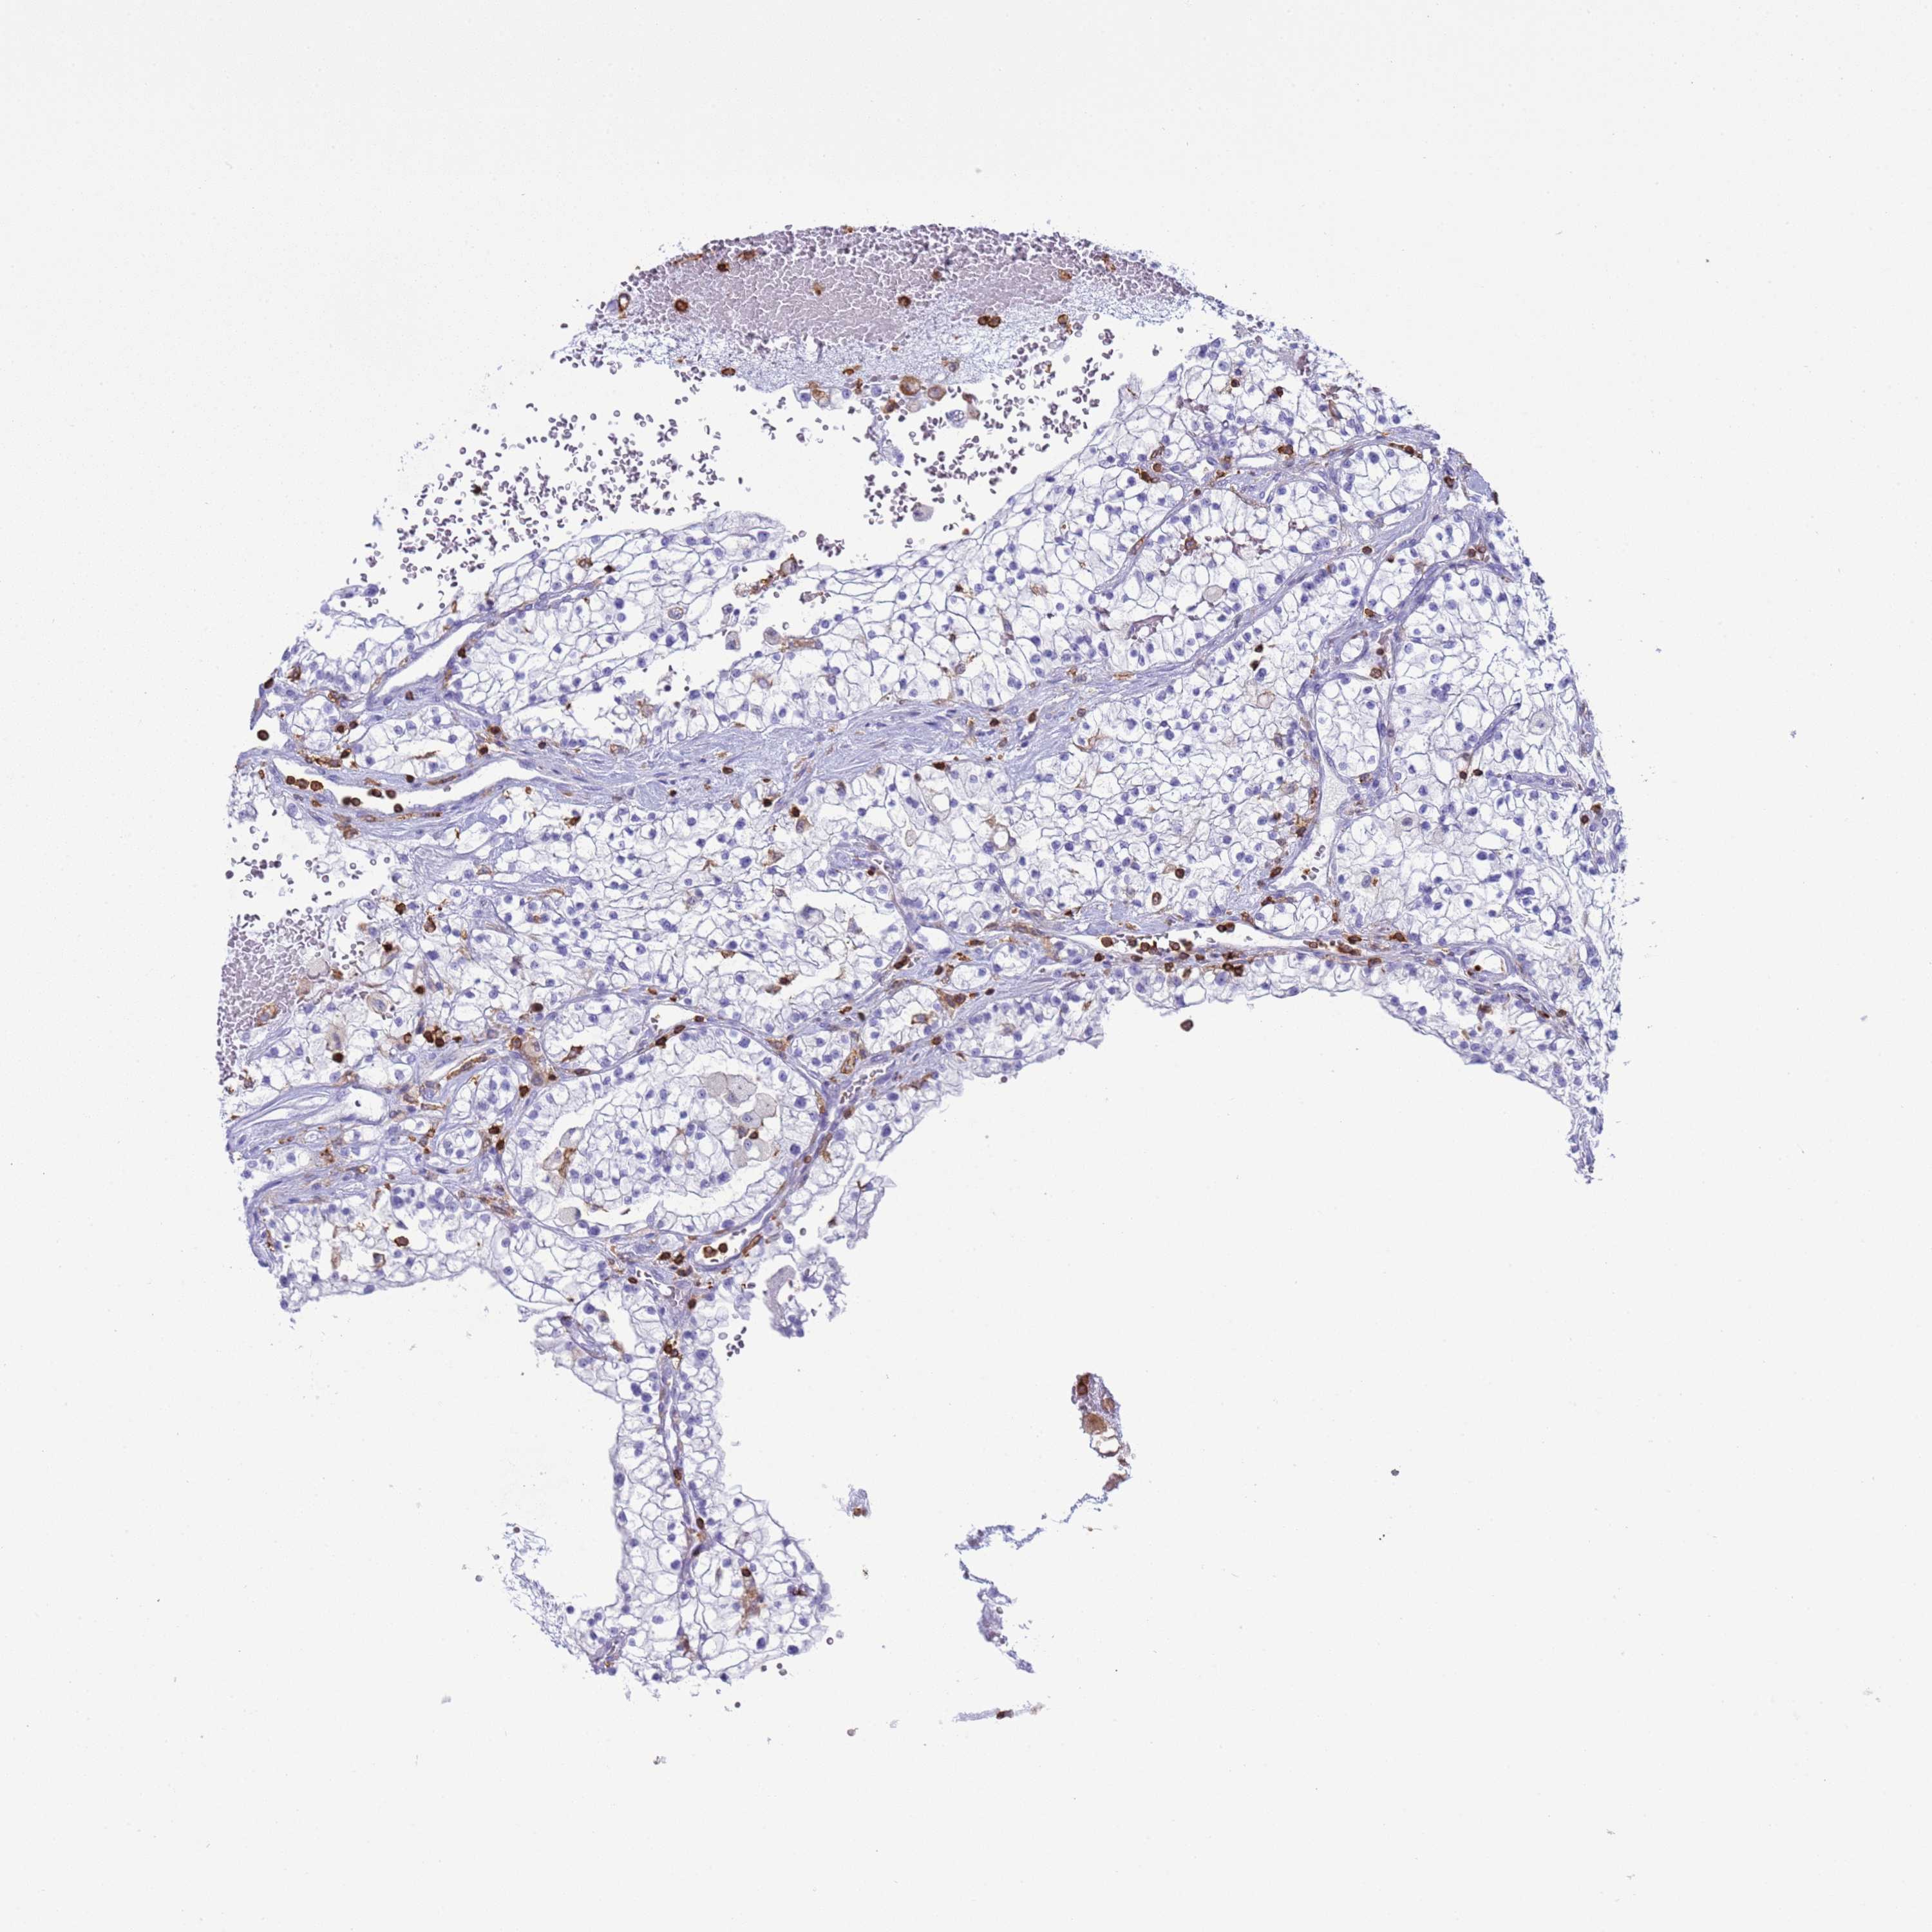

KIDNEY RENAL CLEAR CELL CARCINOMA (VALIDATION) - Interactive survival scatter ploti

The Survival Scatter plot shows the clinical status (i.e. dead or alive) for all individuals in the patient cohort, based on the same data that underlies the corresponding Kaplan-Meier plots. Patients that are alive at last time for follow-up are shown in blue and patients who have died during the study are shown in red.

The x-axis shows the expression levels (FPKM) of the investigated gene in the tumor tissue at the time of diagnosis. The y-axis shows the follow-up time after diagnosis (years). Both axes are complimented with kernel density curves demonstrating the data density over the axes. The top density plot shows the expression levels (FPKM) distribution among dead (red) and alive patients (blue). The right density plot shows the data density of the survived years of dead patients with high and low expression levels respectively, stratified using the cutoff indicated by the vertical dashed line through the Survival Scatter plot. This cutoff is automatically defined based on the FPKM cutoff that minimizes the p-score. The cutoff can be changed by dragging the vertical line or by entering a cutoff value in the square labeled "Current cut-off".

Under the Survival Scatter plot the p-score landscape (black curve; left axis) is shown together with dead median separation (red curve; right axis). Dead median separation is the difference in median mRNA expression between patients who have died with high and low expression, respectively. It is calculated as follows: median FPKM expression of dead patients with high expression - median FPKM expression of dead patients with low expression. This is intended to aid the user in visually exploring custom cutoffs and the associated p-scores and dead median separation.

Individual patient data is displayed and can be filtered by clicking on one or more of the category buttons on the top of the page. Categories describing expression level and patient information include: high, low, alive, dead, female, male and tumor stages. The scale of the x-axis can be toggled between linear and log-scale by clicking on the "x log" button. Mouse-over function shows TCGA ID, patient information and mRNA expression (FPKM) for each patient.

& Survival analysisi

Kaplan-Meier plots summarize results from analysis of correlation between mRNA expression level and patient survival. Patients were divided based on level of expression into one of the two groups "low" (under cut off) or "high" (over cut off). X-axis shows time for survival (years) and y-axis shows the probability of survival, where 1.0 corresponds to 100 percent.

IRF5 is not prognostic in Kidney Renal Clear Cell Carcinoma (validation)

: 20.04

Average pTPM 19.0

Number of samples 100